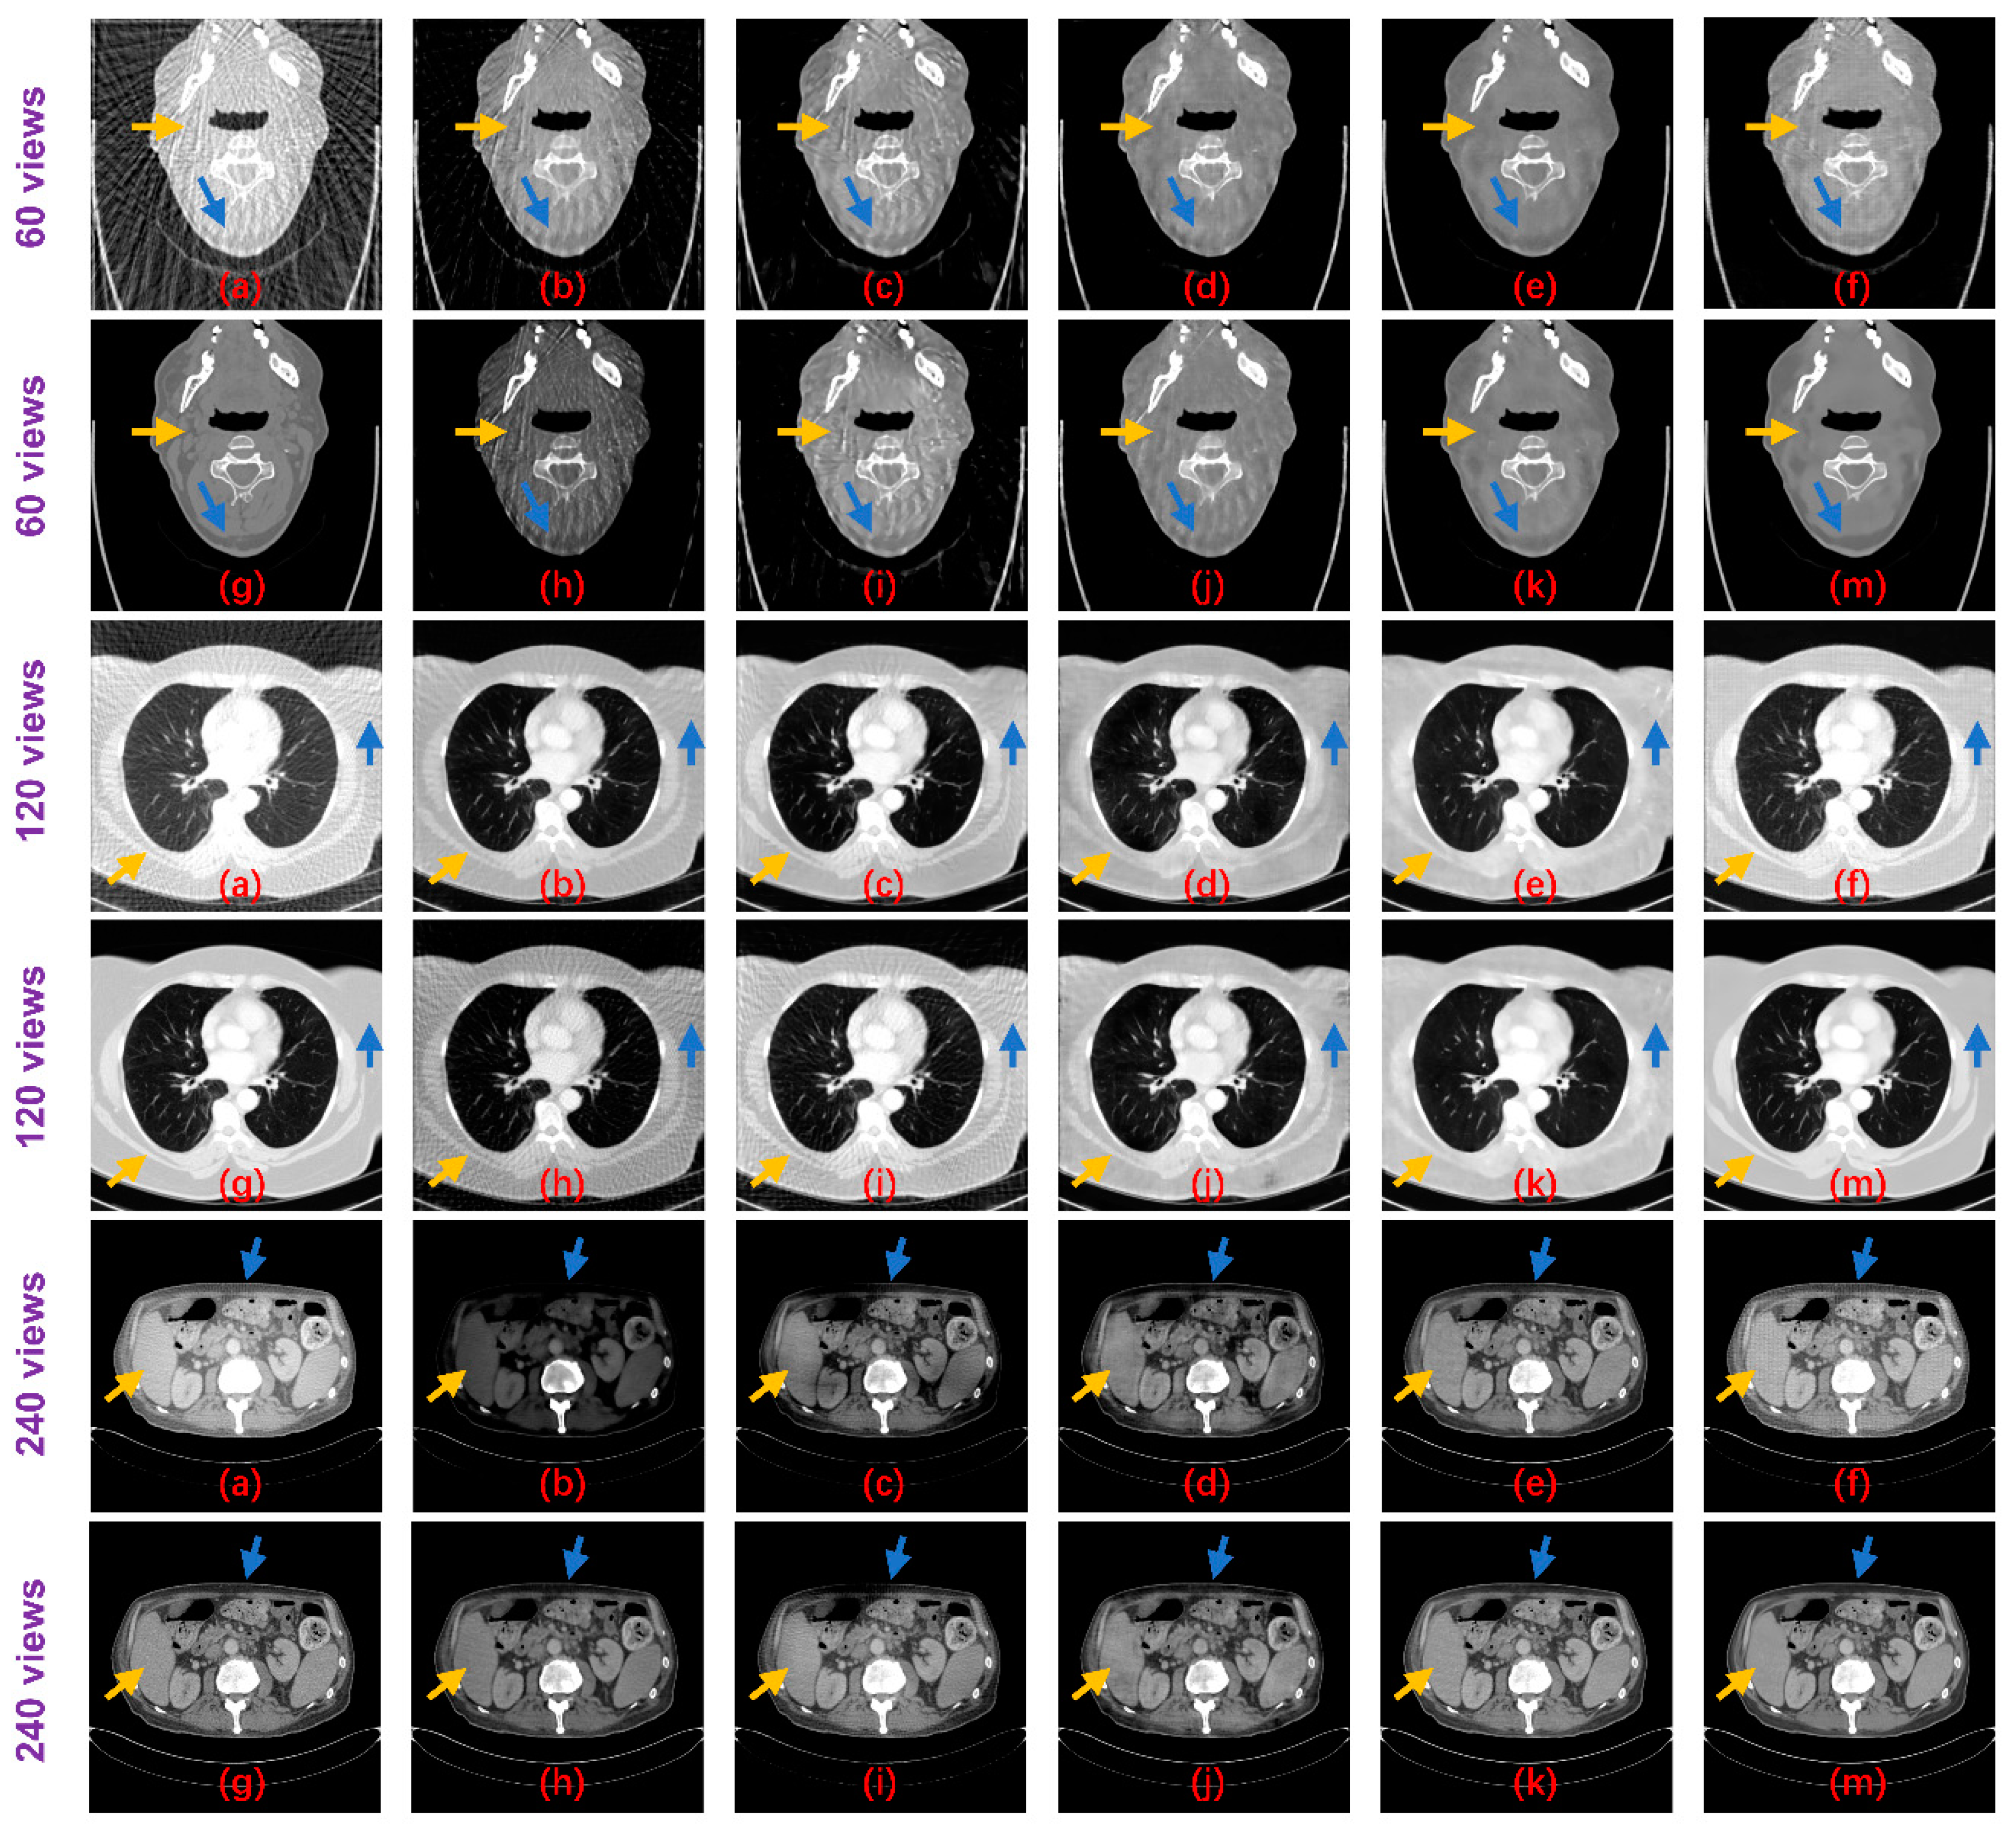

Table 2 shows the PSNR and SSIM results of these methods on the test datasets. Both non-deep learning methods performed worse than the deep learning methods, while for the deep learning algorithms, the Tight frame U-Net achieves higher PSNR and SSIM performance compared to Improved GoogLeNet with 25 times the number of parameters. The RED-CNN achieves better PSNR performance than the Tight frame U-Net, especially on the 60 views dataset and the network parameters are only 6% of the Tight frame U-Net, which we believe may be overfitted. Thanks to DenseNet and deconvolution’s ability to capture deep features of images, DD-NET obtains a better PSNR performance than RED-CNN, especially on the head and abdomen datasets, and higher SSIM, especially on the head and esophagus datasets. Particularly, our method outperforms all methods by achieving optimal PSNR and SSIM performance on all datasets. From the perspective of the degradation level, the PSNR of our method is on average 0.84 dB, 0.89 dB and 1.22 dB higher than DD-Net, respectively, for the 60 views, 120 views and 240 views datasets, and the SSIM results are on average 0.02, 0.01 and 0.01 higher, respectively. In terms of the body part, the PSNRs of our method are 0.89 dB, 0.94 dB, 1.29 dB and 0.80 dB higher than those of DD-Net for the head, abdomen, lung and esophagus, respectively, and the SSIM results are 0.02, 0.01, 0.02 and 0.01 higher, respectively. Figure 8 shows the reconstruction results of these methods. It can be seen that the artifact removal performance and detailed retention performance of our proposed method are optimal for all kinds of sparse-view datasets.

Figure 8. Result images of the proposed method and the compared algorithms (blue and yellow arrows point out the detailed structural differences); (a) FBP; (b) Improved GoogLeNet; (c) Tight frame U-Net; (d) RED-CNN; (e) DD-Net; (f) frequency-domain module (FDM); (g) ground truth; (h) improved GoogLeNet+; (i) tight frame U-Net+; (j) RED-CNN+; (k) DD-Net+; and (m) ours.

For the networks that contain three sets of parameters corresponding to different degradation levels, Improved GoogLeNet+ has a PSNR advantage over Improved GoogLeNet on 60 views and 120 views while SSIM has an advantage only on 60 views. The performance of Tight Frame U-NET+ is generally weaker than that of Tight Frame U-NET, which may be due to the fact that the training dataset of Tight Frame U-NET+ only targets one degradation level, while the training set of Tight Frame U-NET contains three types of degradation, which moderates the overfitting problem to some extent. The average performance of Red-CNN+ and DD-NET+ is better than that of Red-CNN and DD-NET, but still worse than that of our model and more parameters are used. The standard deviations of PSNR and SSIM for our method on the test dataset are shown in Table 3. Suppose the PSNR and SSIM results are both independent samples from a normally distributed population, Table 3 also displays the 95% confidence intervals for PSNR and SSIM results on the test dataset. Figure 9 displays the difference images between the result images and the ideal CT images. It can be seen that the proposed method can reduce the overall intensity error compared to other methods, therefore, achieves better visual performance.